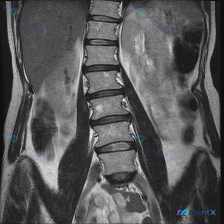

- 序列:腰椎MRI T1加权冠状位

- 核心肉眼/报告所见:腰椎存在向左侧凸出的弯曲,骨性结构(椎体形态、骨髓信号)基本完整,未见明显塌陷、骨质破坏或占位;双侧腰大肌及旁脊肌群大致对称;椎间隙高度大致正常;双侧髂嵴高度基本在同一水平线。

- 局限性:非脊柱全长像,无法精确测Cobb角;单序列,对病理改变敏感度有限。